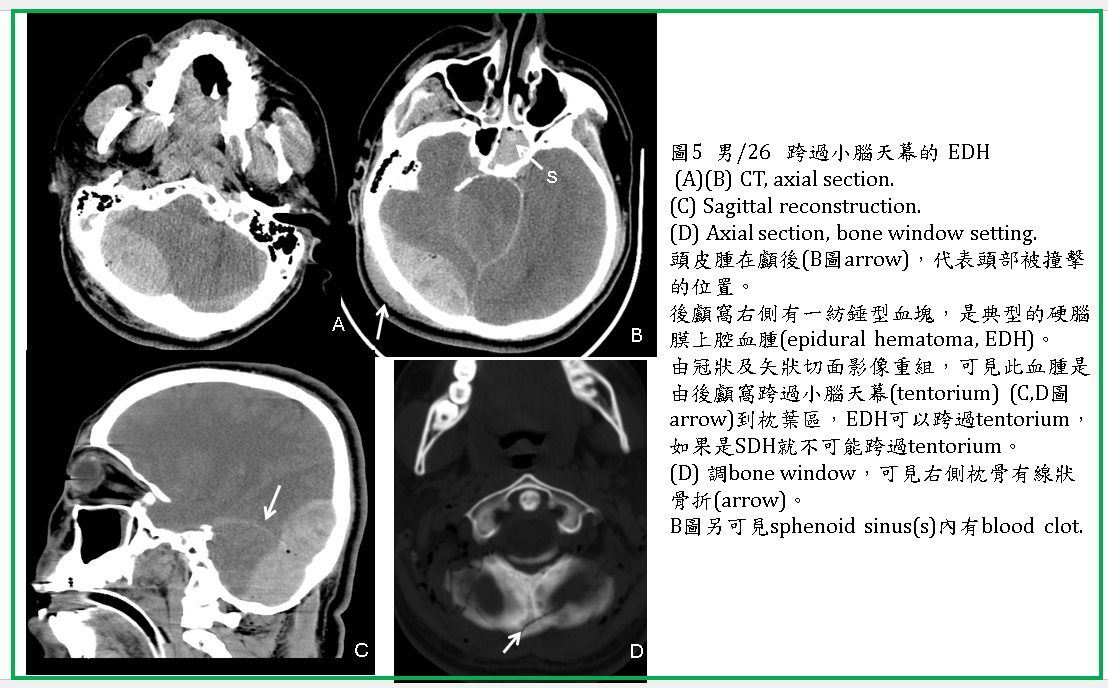

典型的EDH在CT上呈現雙凸形(頭蓋骨與血腫外緣共同構成雙凸形) (圖1-5) ,或稱紡綞形,內為均勻的高濃度血。

EDH通常位於顳、頂葉區,如在額區,可能跨過中線(如falx)到對側(圖4) 。如在後顱窩或枕區,有可能跨過小腦天幕,使小腦天幕上下都有EDH (圖5) 。